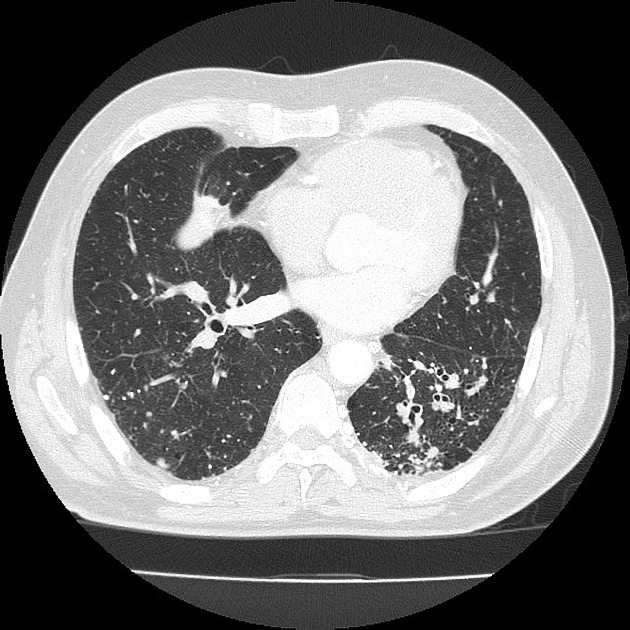

PACIENTE 35 ANOS, SEXO MASCULINO, DISPNÉIA HÁ 4 DIAS.

opacidades em vidro fosco difusas associadas a espessamento de septos interlobulares (crazy paving)

PROTEINOSE ALVEOLAR